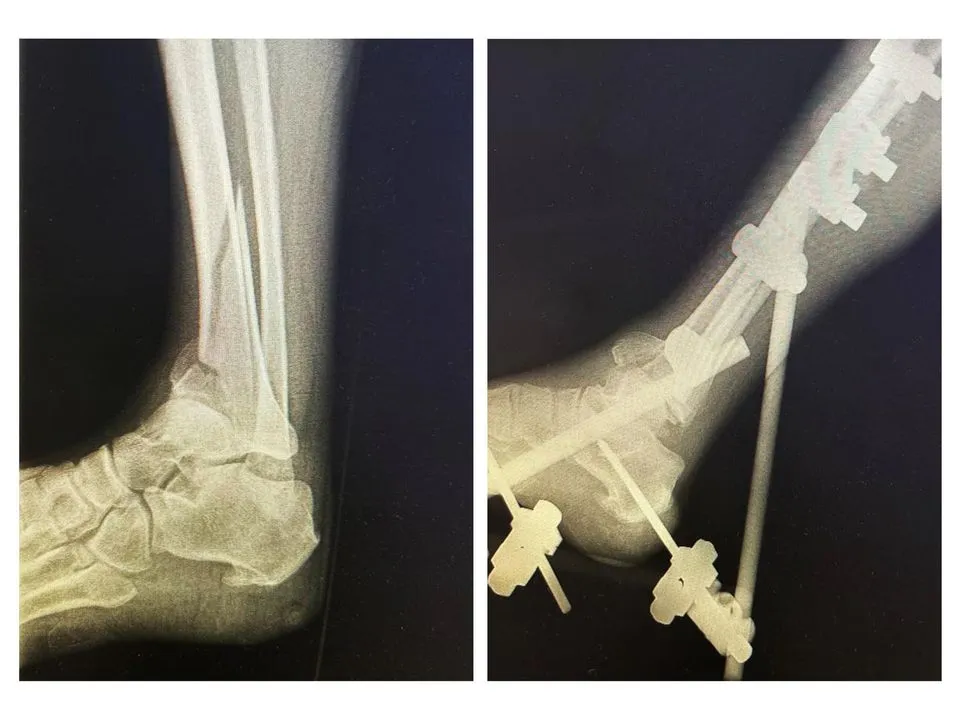

В Солнечногорскую больницу поступила 60-летняя женщина со сломанной ногой. Пациентка страдала от неврологического заболевания, которое мешало ей правильно оценивать свое состояние. Врачи предположили, что травма могла возникнуть вследствие падения.

К моменту поступления в травматологическое отделение повреждение уже не было свежим. Конечность зафиксировали в аппарате наружной фиксации.

По словам врача, совместно с коллегами из других отделений травматологи боролись с сопутствующими заболеваниями, такими как тромбоз нижних конечностей и низкое артериальное давление. После четырех недель интенсивного лечения специалистам удалось провести операцию.

Сейчас пациентка способна самостоятельно передвигаться без опоры на прооперированную ногу и готовится к выписке. Через несколько месяцев она продолжит реабилитацию в отделении реабилитации Солнечногорской больницы.